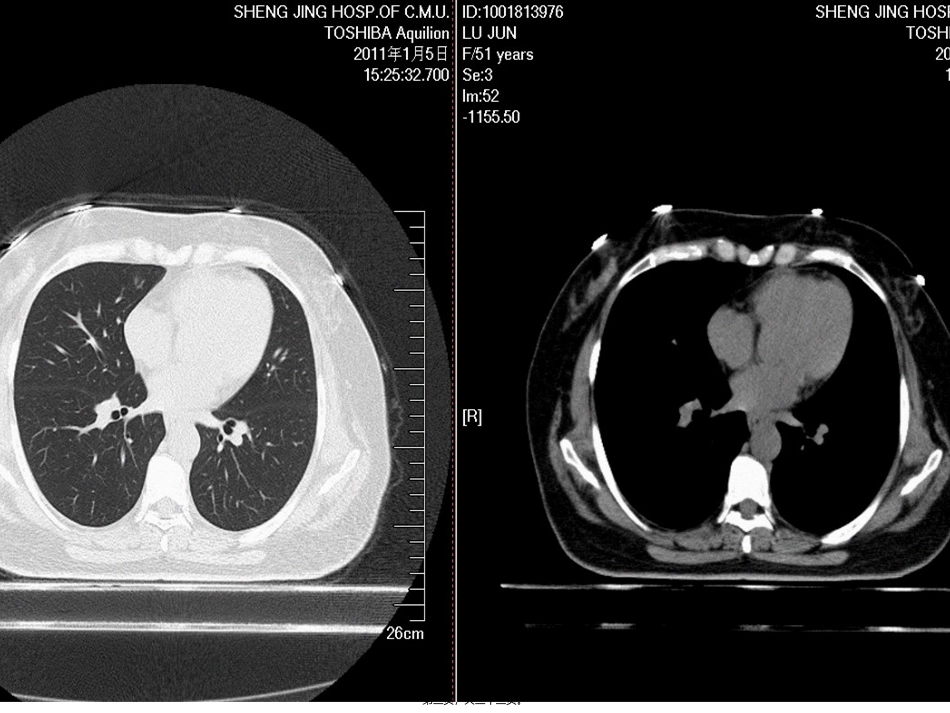

肺癌筛查指南NationalComprehensiveCancerNetworkVersion1.2022第一页,共三十三页。第二页,共三十三页。第三页,共三十三页。第四页,共三十三页。第五页,共三十三页。第六页,共三十三页。第七页,共三十三页。第八页,共三十三页。第九页,共三十三页。第十页,共三十三页。是否为恶性?会不会恶变?需要复查吗?第十一页,共三十三页。美国国家综合癌症网〔NCCN〕指出,在美国和世界其它国家,癌症相关的死亡数量中,肺癌是最主要的死因。据估计2022年,在美国,肺癌将导致156900人死亡〔男性85600,女性71300〕。肺癌的5年生存率仅约15.6%,一局部原因是大局部病人在初次就诊时已是肺癌晚期。第十二页,共三十三页。对子宫颈癌、结肠癌、乳腺癌的筛查以改善疾病预后,这些成功经验是开展一种有效的肺癌筛查测验的推动力。理想目标是,有效的筛查会早期检测出肺癌,并在患者出现病症前,这时治疗更可能有效,减少死亡率。目前,大局部肺癌是在患者有病症时作出临床诊断,如出现咳嗽、胸痛、体重减轻。很不幸,有这些病症的患者通常是晚期肺癌。第十三页,共三十三页。美国NCCN〔国家综合癌症网〕于2022年10月底首次发布了肺癌筛查指南,指南的发布是基于新英格兰医学杂志〔NEJM〕于2022年8月发表的美国国立肺癌筛查研究〔NLST〕的结果。该研究对高危人群应用低剂量螺旋CT〔LDCT〕做每年常规检查,结果发现,与胸片体检相比,LDCT体检可以使肺癌死亡率降低20%,使任何原因死亡率降低7%。基于这一结果,指南中明确将LDCT作为肺癌筛查手段,并对LDCT上的不同发现做出了不同的处理指南。第十四页,共三十三页。总的来说,NCCN指南建议对肺癌高危人群每年进行肺部低剂量螺旋CT检查。高危人群是指:A.55-74岁,正在吸烟或者戒烟少于15年,并且吸烟指数大于30包年。B.年龄≥50岁,吸烟指数≥20包年,并且合并以下情况之一者:肿瘤病史;肺病史;家族中有肺癌患者;住所氡暴露和致癌物质的职业性暴露〔包括砷、铬、石棉、镍、镉、铍、二氧化硅和柴油烟气〕。以上肺癌高危人群建议每年行低剂量螺旋CT〔LDCT〕检查,最少3年〔最佳答案持续年限尚不清楚〕。第十五页,共三十三页。中危人群:年龄≥50岁,吸烟指数≥20包年,或有二手烟暴露,没有附加的危险因素。低危人群:年龄<50岁和/或吸烟指数<20包年。以上不推荐常规肺癌筛查第十六页,共三十三页。根据CT检查结果不同采取不同的处理措施A.未发现肺部结节:每年LDCT检查,至少持续3年〔最佳答案持续年限尚不清楚〕。第十七页,共三十三页。B.发现肺部实性或局部实性结节〔无良性钙化、脂肪或炎性表现的结节〕:a.≤4mm,每年LDCT检查,至少持续3年〔最佳答案持续年限尚不清楚〕b.>4—6mm,6个月后复查LDCT,如无增长,12个月后复查LDCT,仍无增长,每年复查LDCT,至少2年〔最佳答案持续年限尚不清楚〕12个月后复查,如有增长,推荐外科切除第十八页,共三十三页。c.>6—8mm,3个月后复查LDCT,如无增长,6个月后复查LDCT,无变化那么12个月后复查LDCT,仍无变化,每年复查LDCT,至少2年〔最佳答案持续年限尚不清楚〕。6个月后复查LDCT,如有增长,推荐外科切除第十九页,共三十三页。d.>8mm,考虑PET/CT检查,如疑心肺癌,手术或活检。活检结果不是肺癌,每年复查LDCT,至少2年〔最佳答案持续年限尚不清楚〕证实肺癌,参照NCCN非小细胞肺癌指南。不考虑肺癌,动态观察同上。以上情况在动态观察中,如发现结节增长,建议手术切除。第二十页,共三十三页。e.发现支气管内结节,1个月后复查LDCT,出现剧烈咳嗽应立即复查。如无消退,做纤维支气管镜检查明确。第二十一页,共三十三页。C.发现肺部磨玻璃影〔GGO〕或其他非实性结节〔无明确良性指证〕:a.<5mm,12个月后复查CT,如稳定,每年LDCT检查,至少持续2年〔最佳答案持续年限尚不清楚〕。增长和/或变为实性或局部实性:3-6个月后复查LDCT或考虑外科切除。活检结果不是肺癌,每年复查LDCT,至少2年〔最佳答案持续年限尚不清楚〕。证实肺癌,参照NCCN非小细胞肺癌指南。第二十二页,共三十三页。b.5-10mm,6个月后复查CT,如稳定,每年LDCT检查,至少持续2年〔最佳答案持...